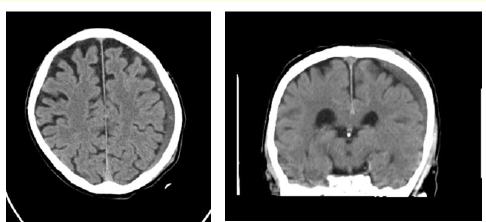

Case Report

Asymptomatic Intracerebral Hemorrhage Under Rivaroxaban

Ekkehard Pietsch. 12(5): 54-59.